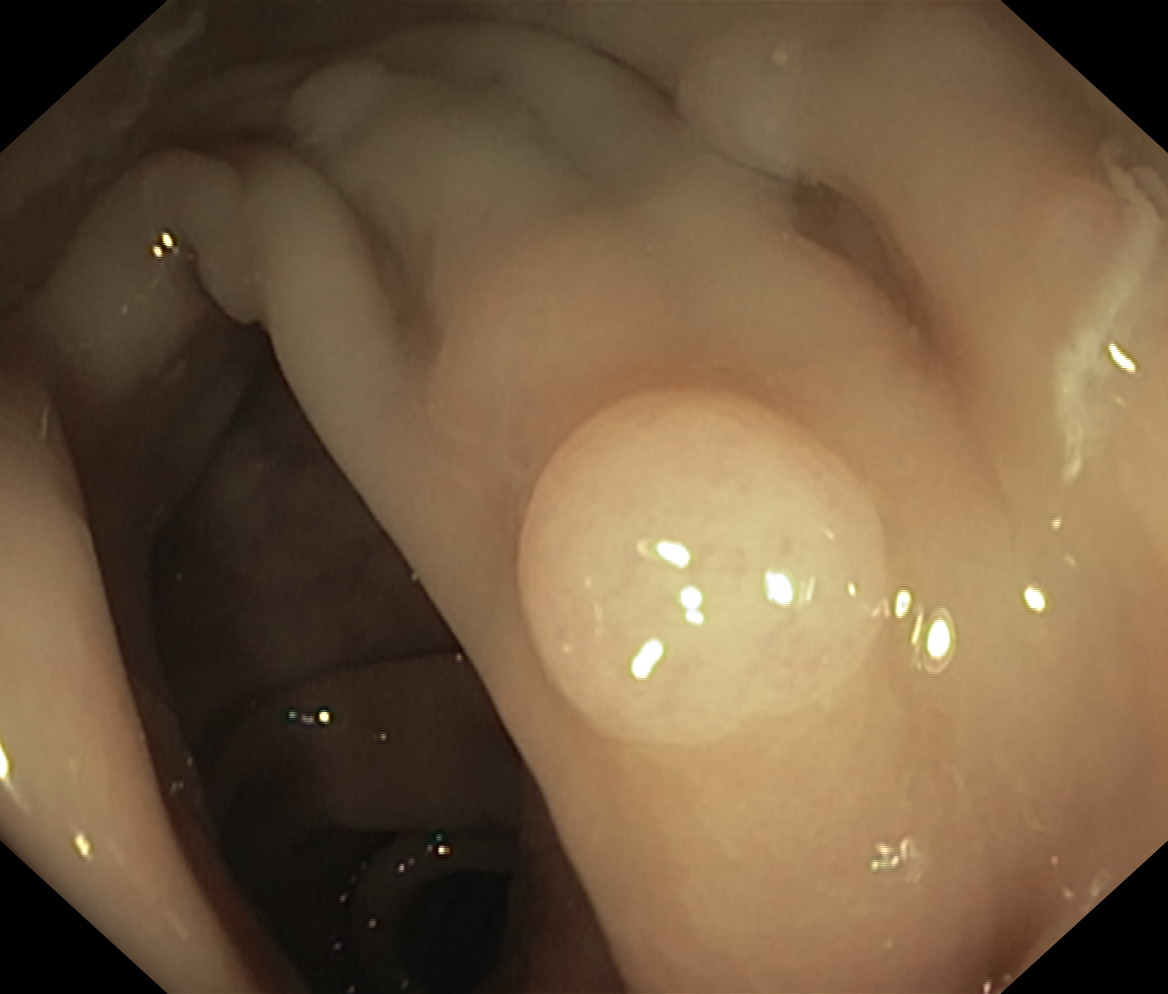

Polipy